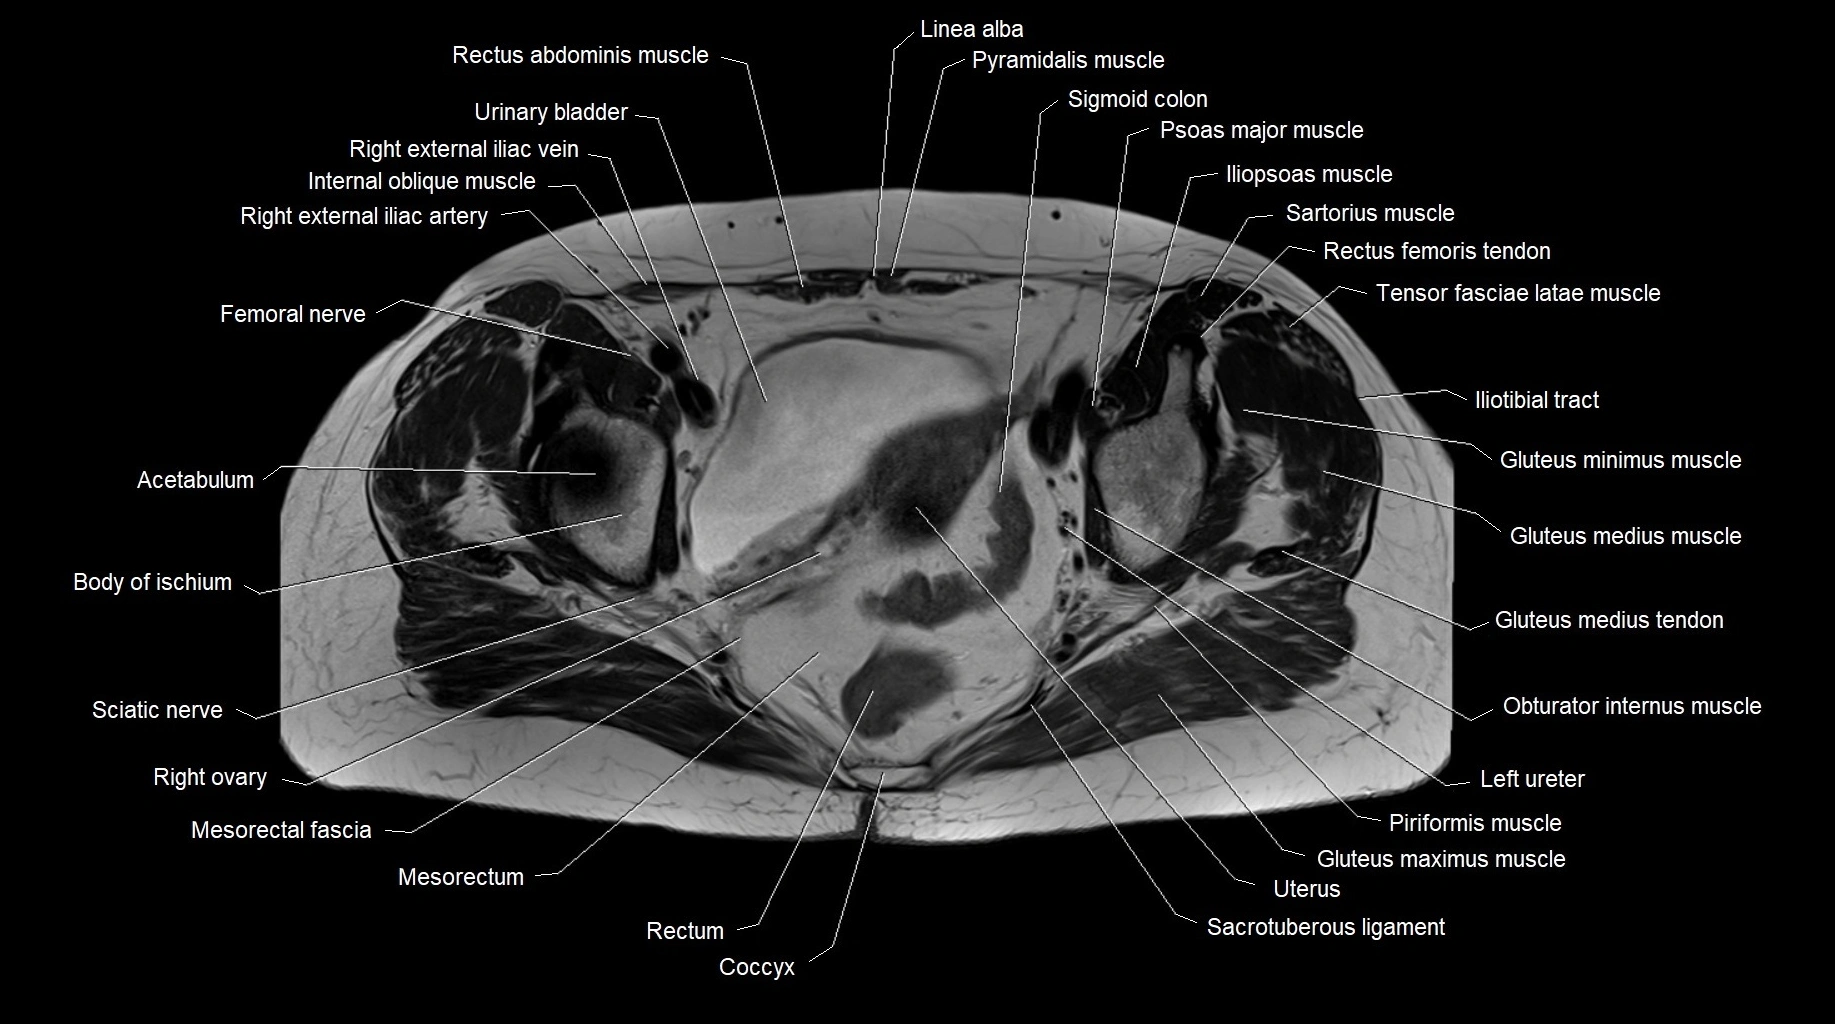

MRI images